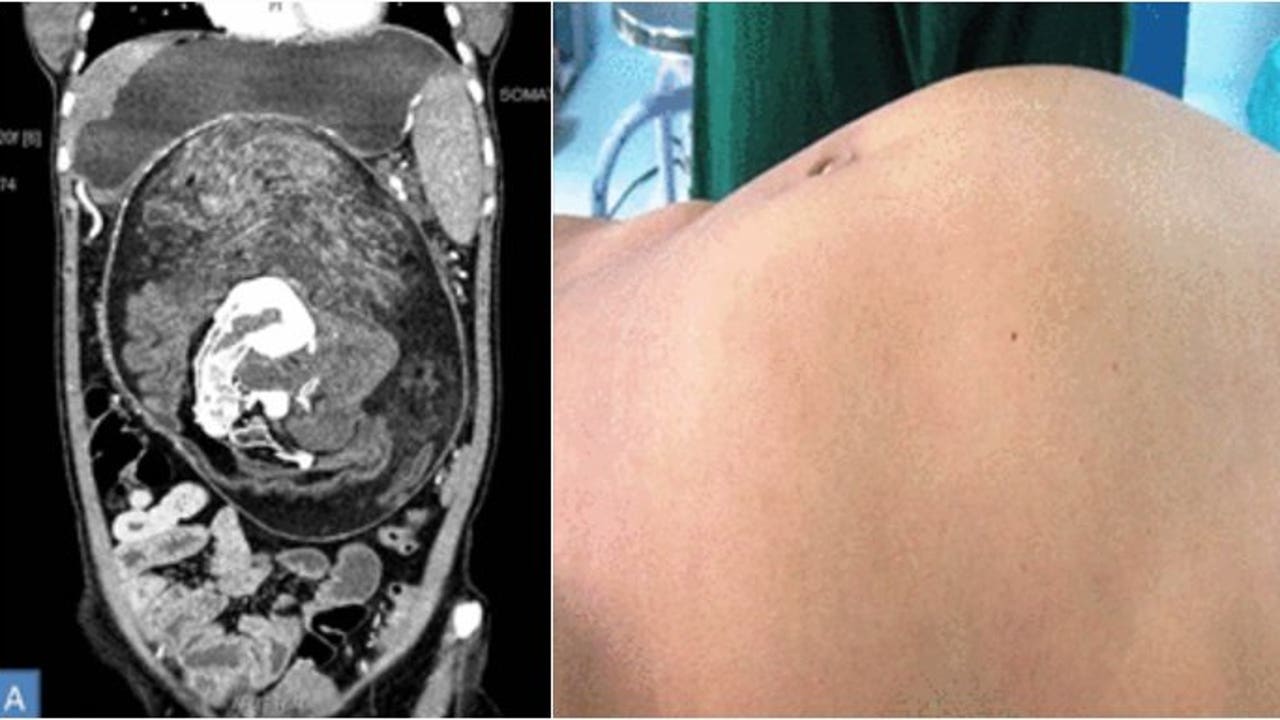

More precisely, the mass measuring 14 by 6 by 4 inches contained apparent ribs and vertebrae along with "multiple teeth and structures resembling limb buds," per an analysis in BMJ Case Reports.

The 17-year-old had complained about a growing abdomen lump that sometimes caused her pain or the feeling of being full. After a CT scan, doctors diagnosed her with fetus in fetu, a rare condition in which an oddly developed fetus is found inside a person's body. Why it occurs is unclear.